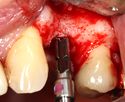

A series of slow-speed drills create and gradually enlarge a site in the jaw for the implant to be placed. The hole is called an osteotomy.

Once the bone is exposed, a series of drills create and gradually enlarge a site (called an osteotomy) for the implant to be placed.

The implant fixture is turned into the osteotomy. Ideally, it is completely covered by bone and has no movement within the bone.